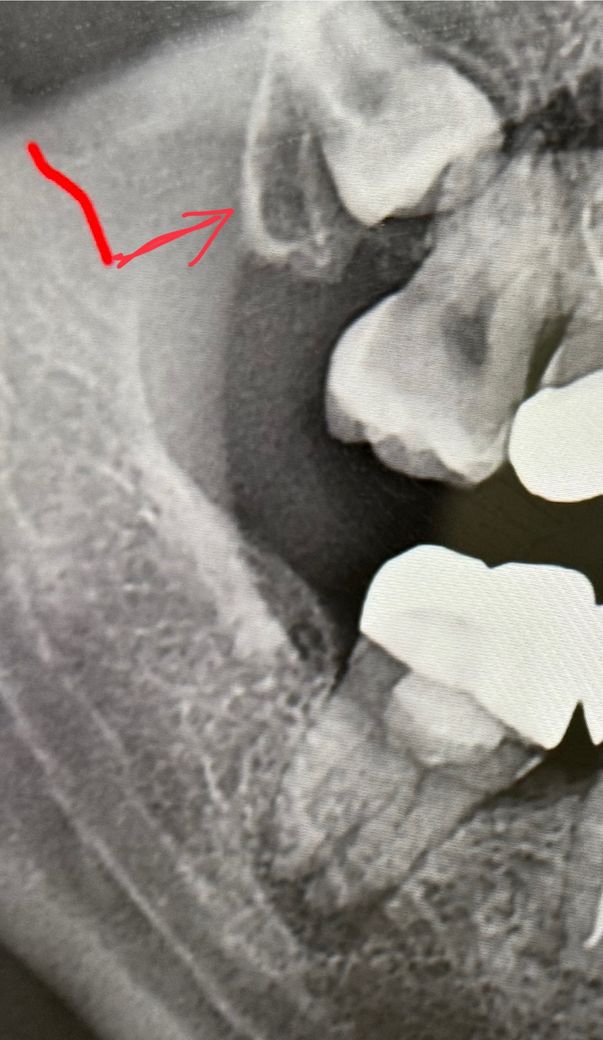

이런 사랑니 대학병원에 가서 빼야 하나요?

사랑니 위치가 안 좋아서 치과에서 대학병원 가서 빼라고 하는데, 아무 이상 없으면 그냥 살아도 괜찮나요?

앞쪽 이빨을 누르고 있는 것 같은데 딱히 아프거나 그러진 않아요.

지금은 사랑니 보다 사랑니 바로옆 어금니의 손상이 큰 것으로 보입니다. 이런 경우 사랑니 빼게 되면 어금니가 흔들거려 어금니도 같이 빼는 경우가 종종 발생합니다. 대학병원 가더라도 이런 케이스는 그냥 두고 쓰는데 까지 쓰다가 바로옆 어금니가 아프면 어금니를 빼라고 할 것으로 보입니다. 대학병원 아니더라도 구강외과 전문의에게 사랑니 진료 받는 것을 추천합니다.

1. 실제로 어느정도 겹쳐있는지는 3d사진인 ct를 봐야 알고요. 저래 봐서는 다 겹쳐서 정확히 알 수가 없습니다.

3. 특별히 위험한 해부학적 구조가 있어서 그런건 아니고 뼈를 좀 쳐야합니다.